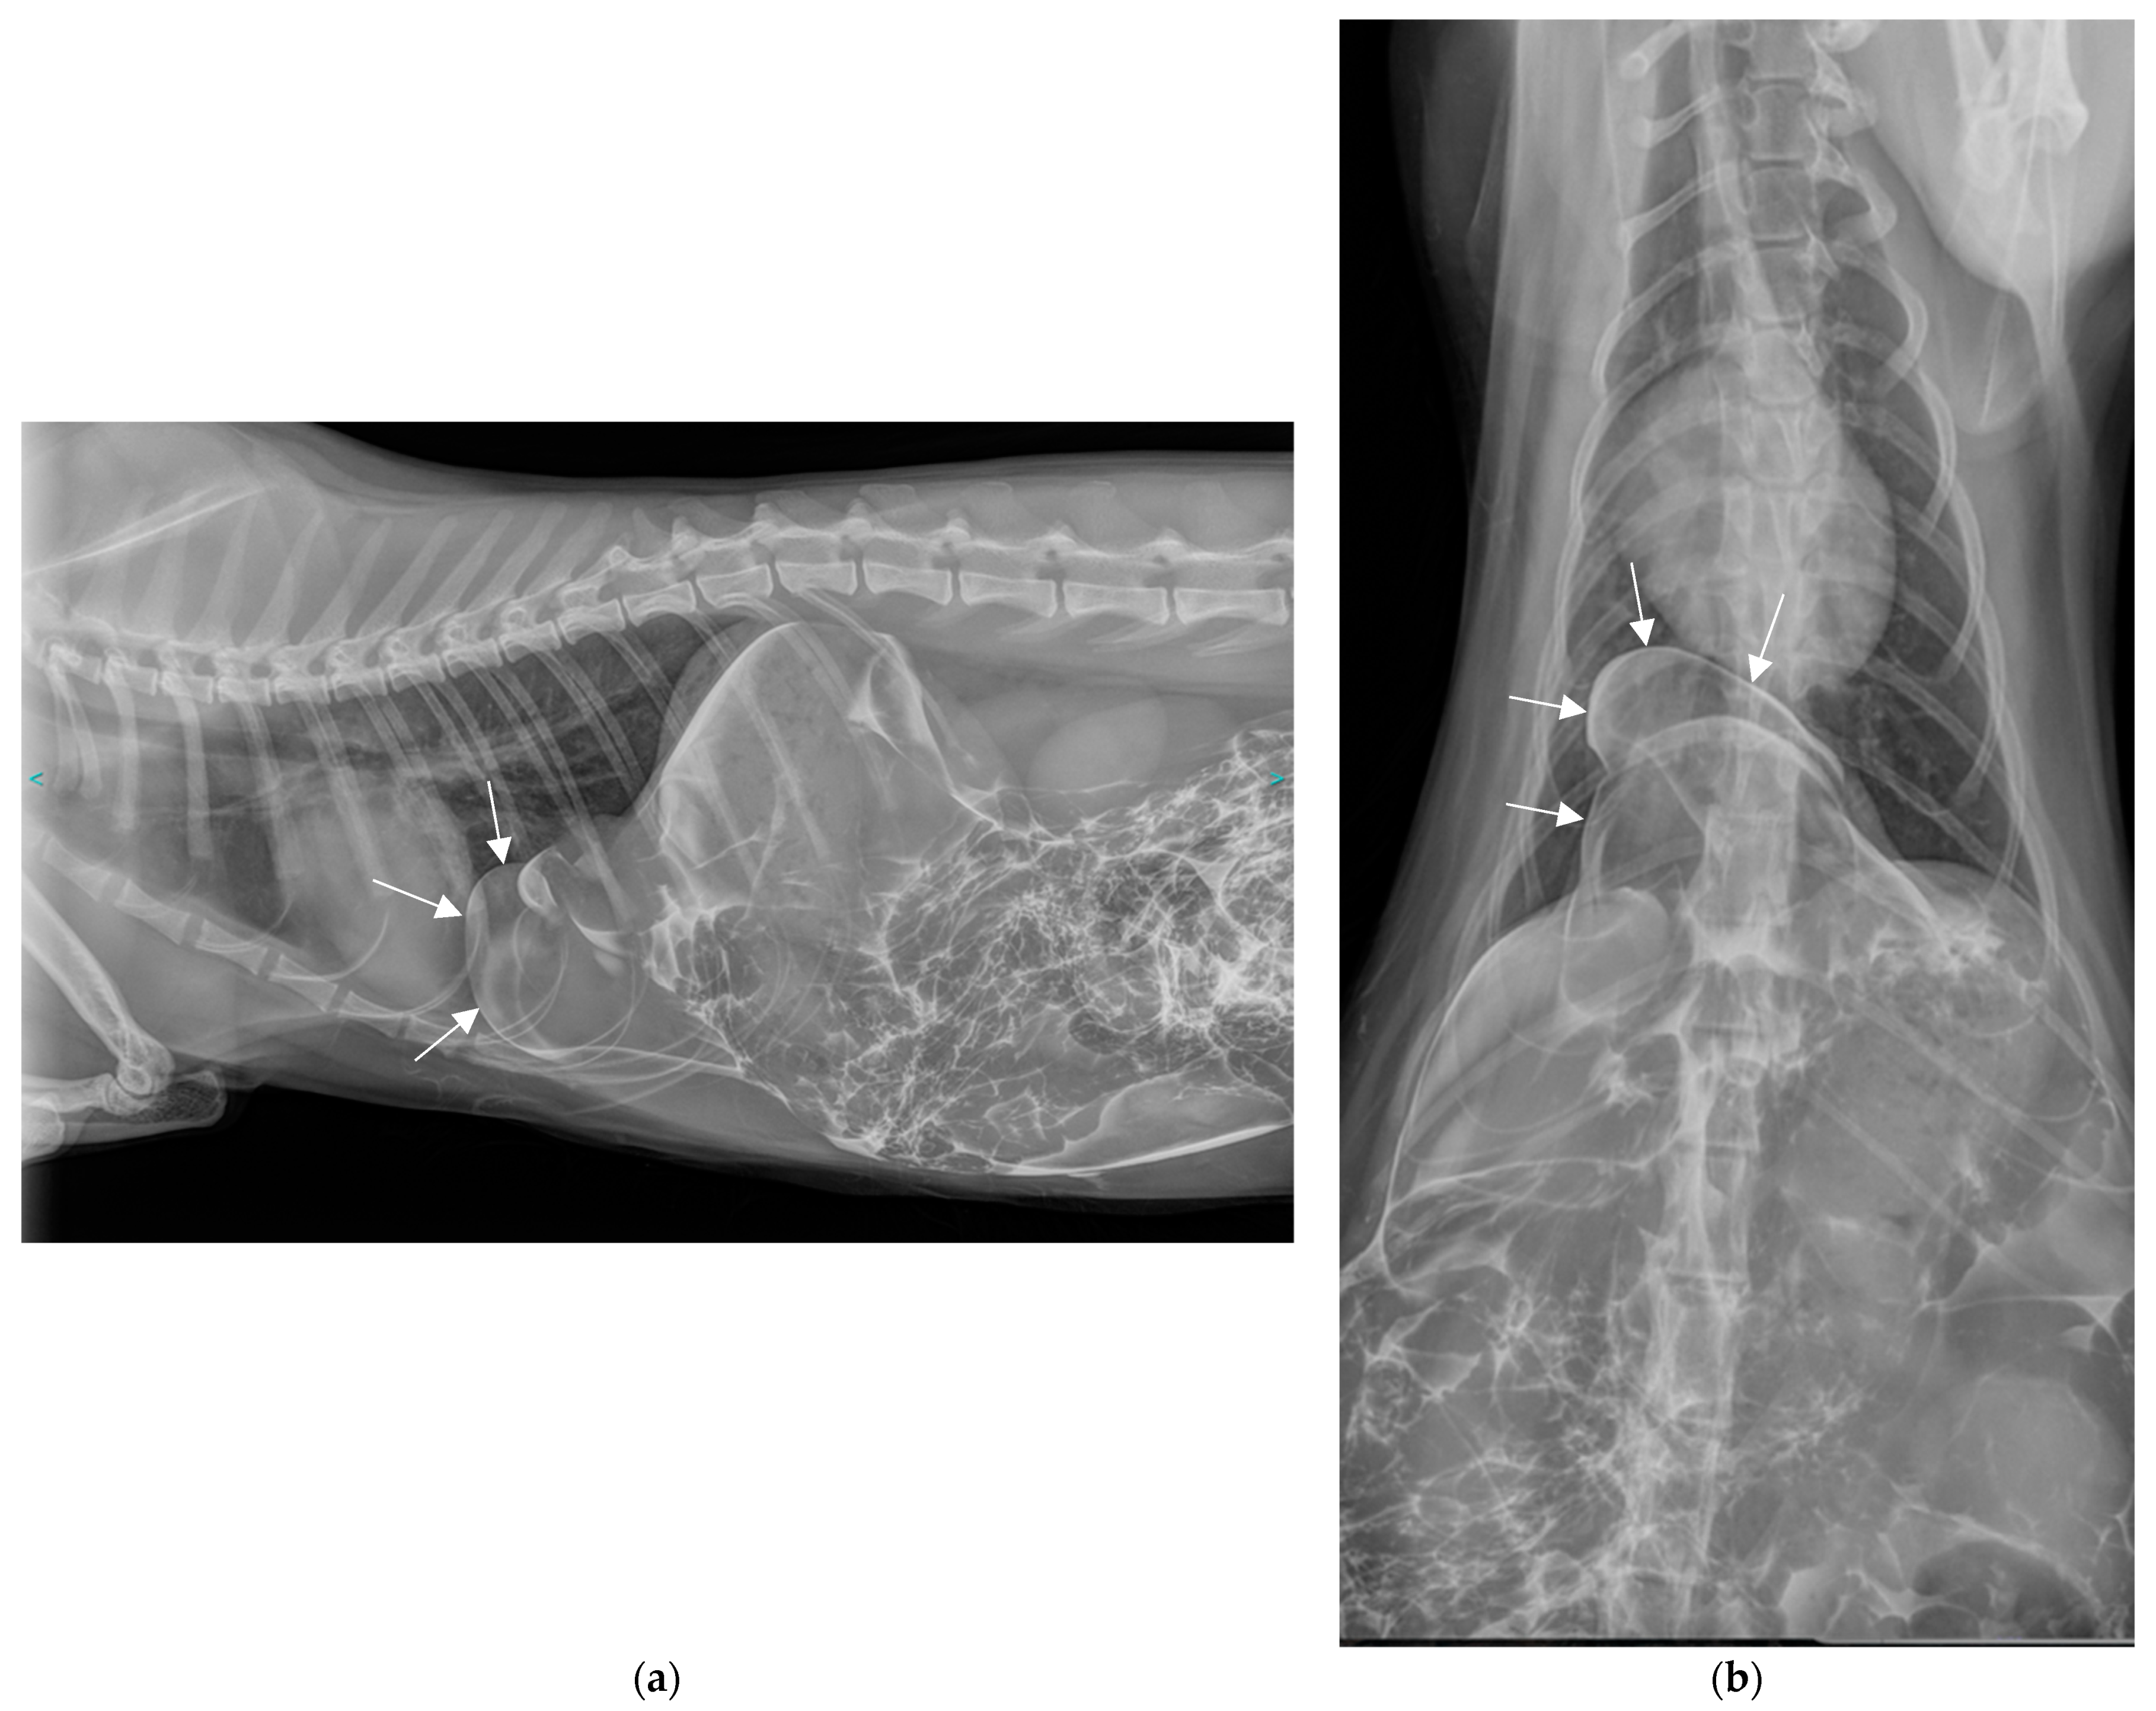

2.2. Additional Tests

2.3. Diagnosis

3.5. Positive Contrast Peritoneography